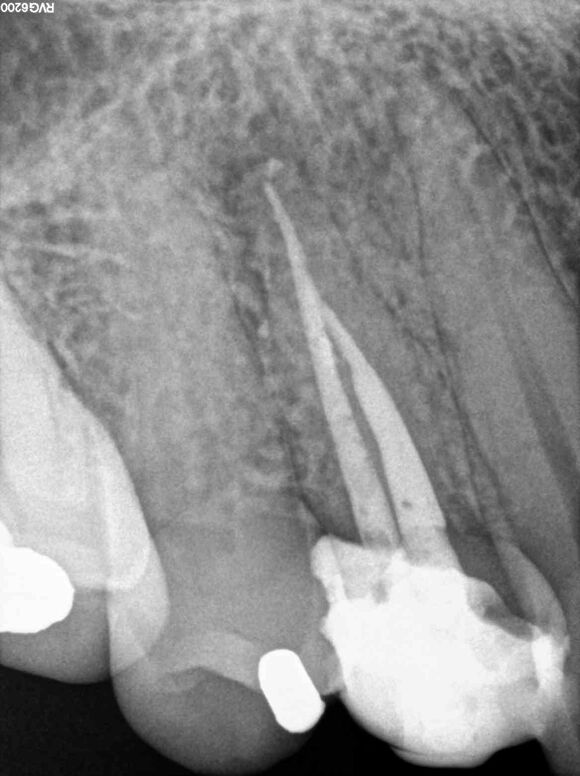

Beispiel 4: Vorher

Unvollständige Wurzelbehandlung und abgebrochenes Instrument.

Beispiel 4: Nachher

Instrument entfernt, Wurzelfüllung optimiert und Entzündung in Rückbildung.